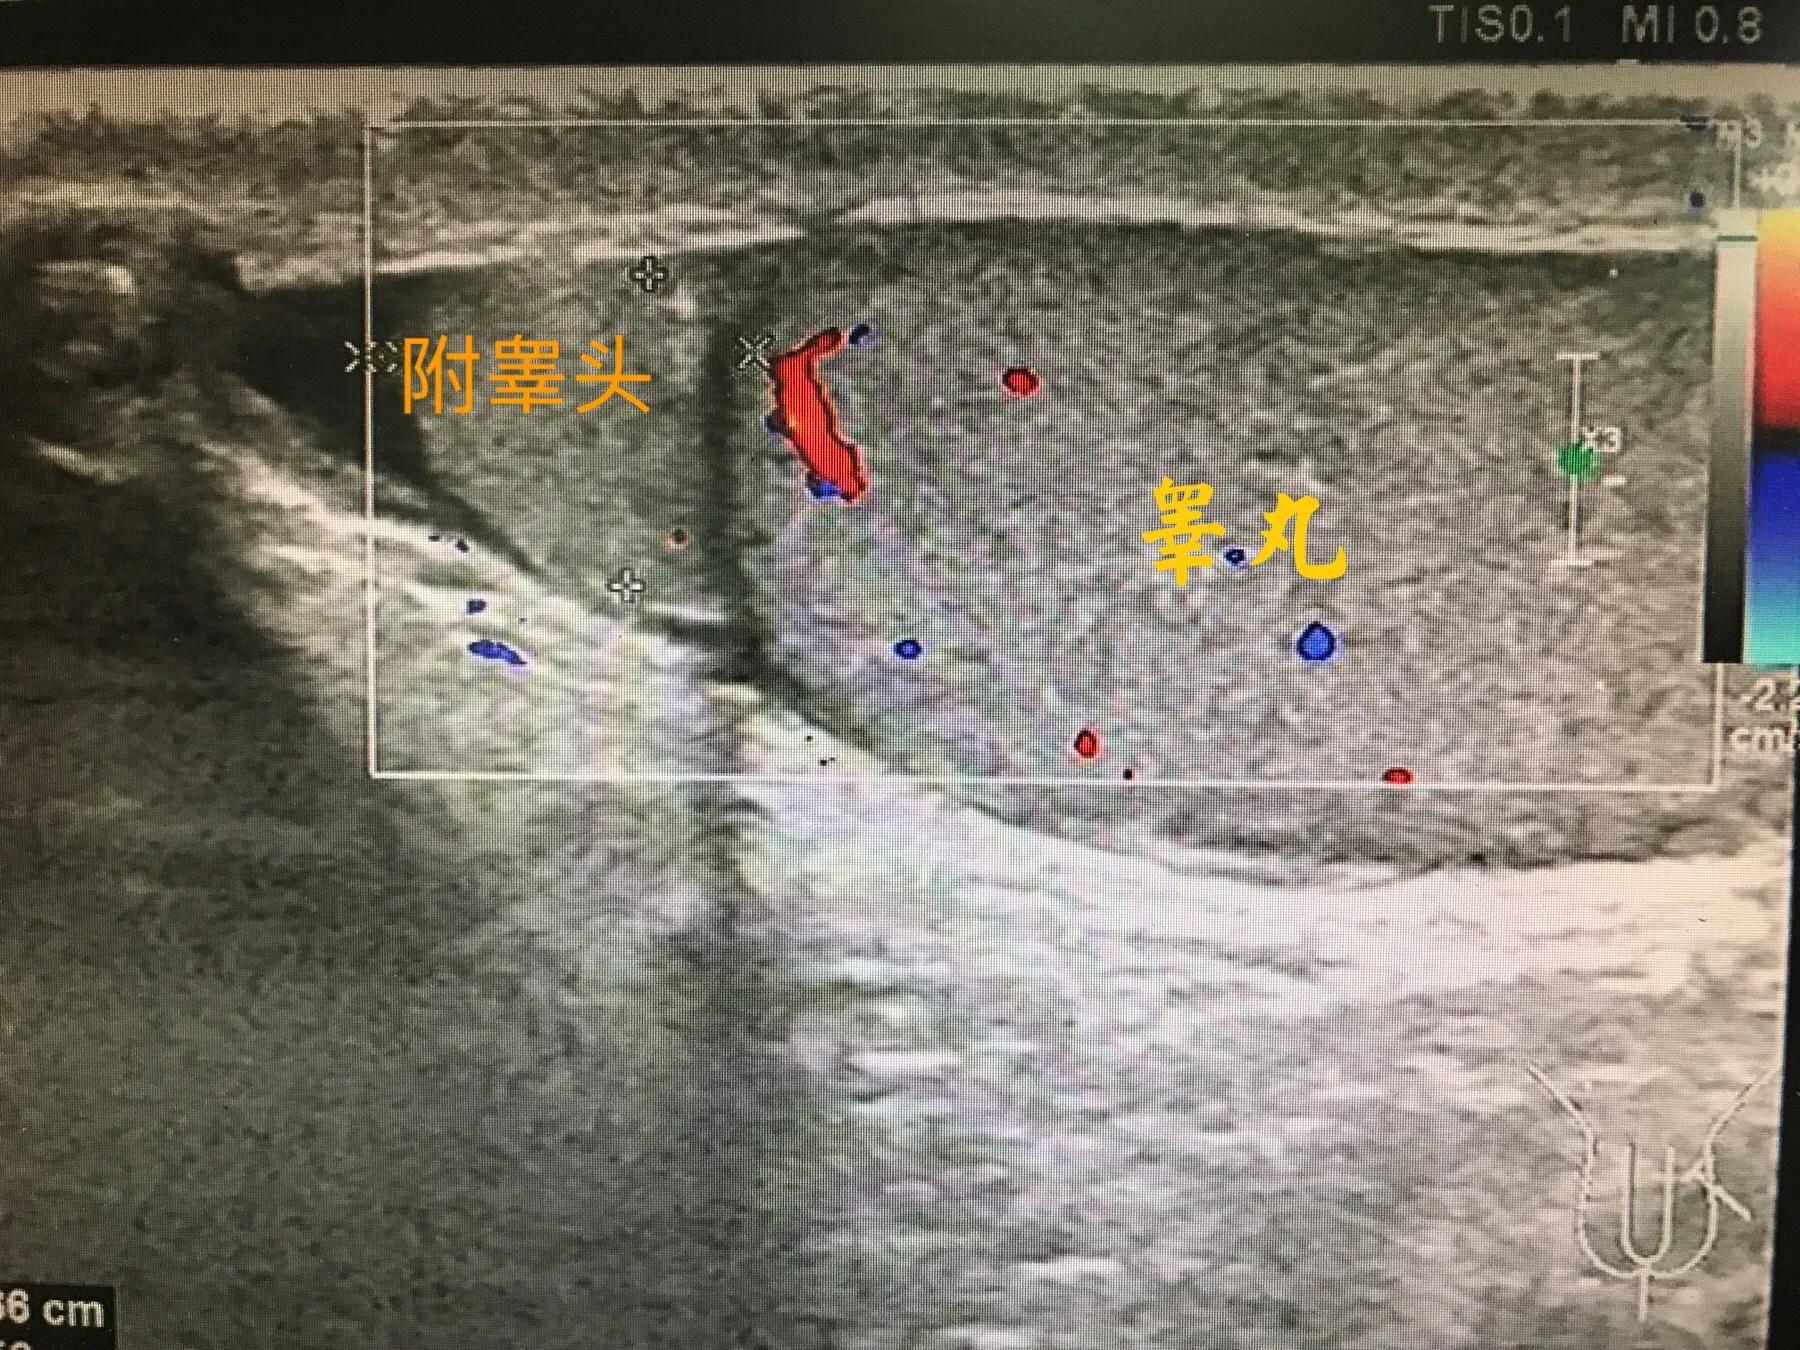

正常成年男性*丸睾**大小约长4CM、厚约2CM、宽约3CM,*丸睾**外面有一层包膜,内部为*丸睾**实质,回声均匀,内部会有稀疏的血量信号。影响*丸睾**大小的原因有:*丸睾**炎、*丸睾**肿瘤、*丸睾**囊肿等。还有就是*丸睾**的周围还趴着一个附睾,附睾也是生殖系统重要的器官之一,它分为头、体、尾部。